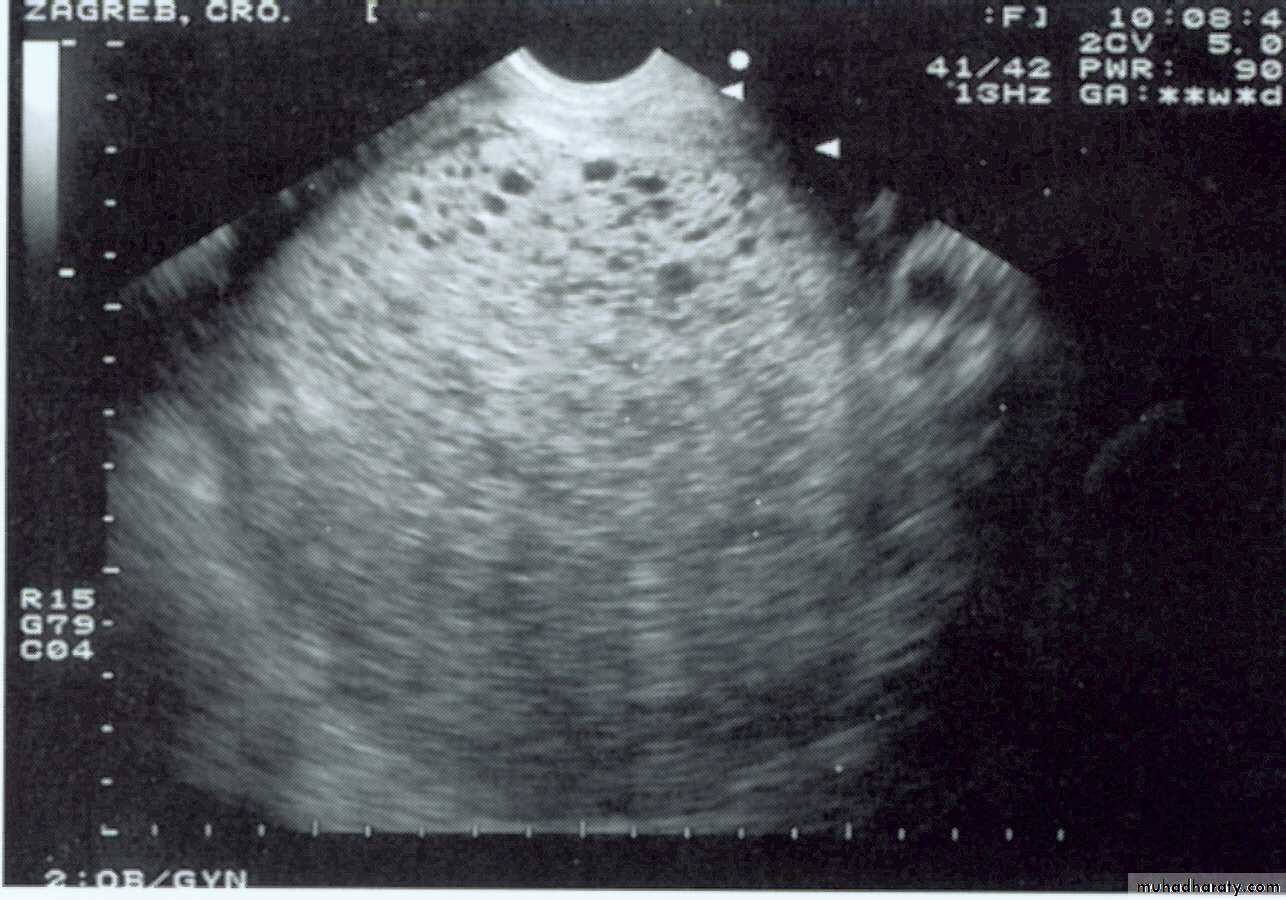

Complete Hydatidiform Moleallows identification of numerous, discrete, anechoic (cystic) spaces within a central area of heterogeneous echotexture

Complete hydatidiform mole demonstrating enlarged villi of various size

Complete Hydatidiform Mole

Theca lutein cysts

multiloculated,

often bilateral

resolve after treatment of the intrauterine process